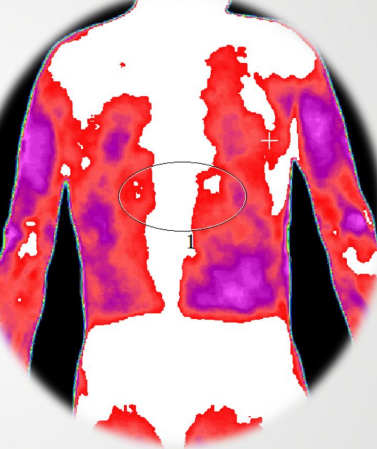

2、受损程度的反馈

肾结晶

肾结石

通过图片画圈地方显示很明显的就会看出哪里出现症状。